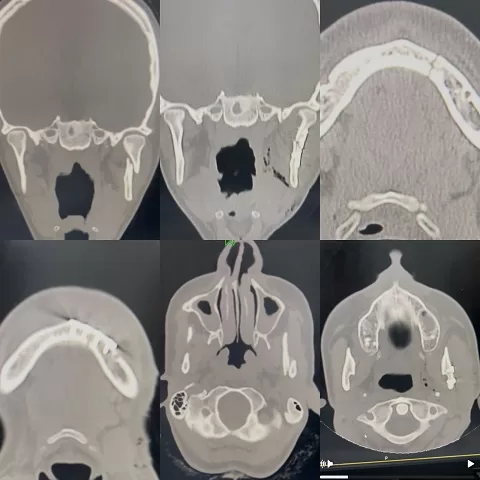

- الحالة الأولى (كسور الفك المركبة): لمريض كان ينتظر الجراحة في مستشفى آخر لمدة ثلاثة أسابيع إثر تعرضه لحادث. تم تشخيص حالته في مستشفى شربين بكسر في عنق اللقمة للفك السفلي وكسر أمامي بالفك.

- الإجراء الجراحي: أُجريت الجراحة بنجاح عبر شق تجميلي خلف الفك للوصول إلى المفصل، وشق داخلي داخل الفم لعلاج الكسر الأمامي. تم تثبيت الكسور بشرائح ومسامير معدنية دقيقة، مع استعادة الإطباق الطبيعي للفك. وقد خرج المريض بعد استقرار حالته تمامًا.